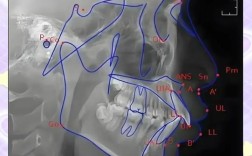

正畸头影测量是口腔正畸学中通过分析颅颌部X线影像进行定量诊断的核心技术,其指标涵盖骨骼、牙齿及软组织多个维度,其中z角作为评估软组织侧貌的关键参数,对正畸治疗方案设计和疗效预测具有重要指导意义,z角又称软组织面角,由软组织颏前点(Pos)与...